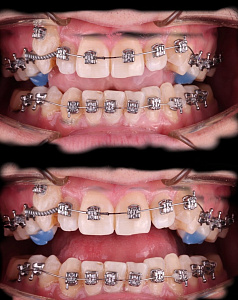

Гегиров Амир Артурович (@amir__ortodont)

Врач-ортодонт

#repost от @amir__ortodont

Была проведена полная фиксация брекетов на обе челюсти, установлены дуги и дополнительные элементы для запуска контролируемого перемещения зубов. Уже с первых месяцев лечения начинается работа над выравниванием зубных рядов, подготовкой места для правильного положения клыков и коррекцией прикуса.

В данном случае наблюдается выраженный дефицит места для клыков, поэтому лечение будет проходить поэтапно и с использованием дополнительной опоры. Каждый элемент системы работает на прогнозируемый и максимально эффективный результат.

Была проведена полная фиксация брекетов на обе челюсти, установлены дуги и дополнительные элементы для запуска контролируемого перемещения зубов. Уже с первых месяцев лечения начинается работа над выравниванием зубных рядов, подготовкой места для правильного положения клыков и коррекцией прикуса.

В данном случае наблюдается выраженный дефицит места для клыков, поэтому лечение будет проходить поэтапно и с использованием дополнительной опоры. Каждый элемент системы работает на прогнозируемый и максимально эффективный результат.